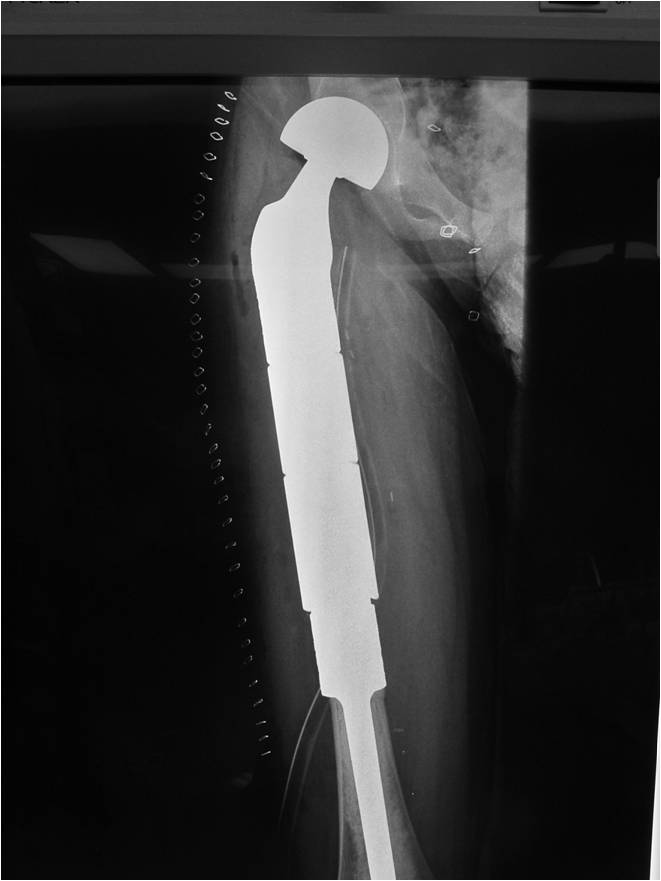

- Most protocols administer preoperative chemotherapy then surgery is performed. Surgery is followed by several courses of postoperative chemotherapy.

- Surgical resection

- Limb sparing surgery whenever feasible unless there will be a large leg length discrepancy that can not be accomodated for with surgery

- Rarely ever an amputation since Ewing sarcoma are sensitive to radiation

If surgical resection is not feasible, radiation may be utilized for local control (instead of an amputation) since Ewing sarcoma is highly sensitive to radiation, at least as per the author’s opinion. There may be some tumors that are selectively treated with radiation instead of surgery however most patients as of 2008 are treated with limb sparing surgery whenever feasible. Sometimes radiation is used in conjunction with surgery if a wide margin was not obtained at the time of surgery. The decision to administer radiation depends on size of tumor, site of tumor, response of tumor to preoperative chemotherapy and risks vs benefits of radiation.